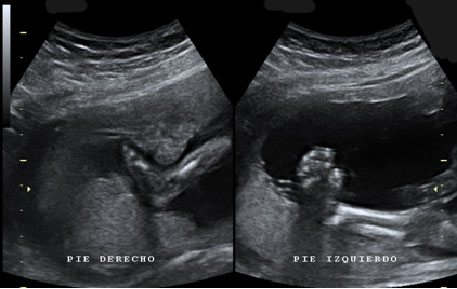

Ecografía de bebé de 20 semanas de perfil

Podemos ver claramente los miembros superiores: el feto flexiona los brazos y los pasa por delante de la cara